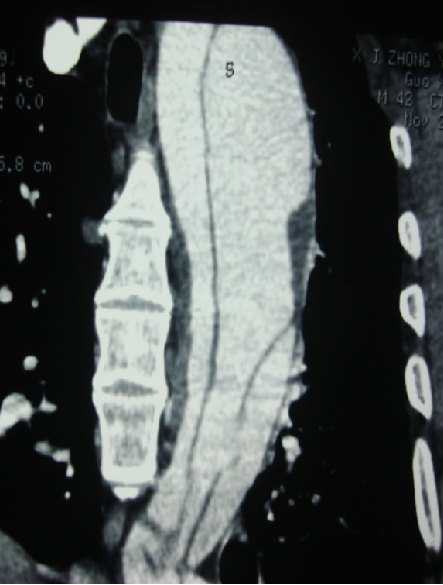

男, 49岁,急性夹层 。2018年11月TEVAR。一月后复查:RTAD 。 2019年1月双开窗。2019年4月2日 复查,结果良好。